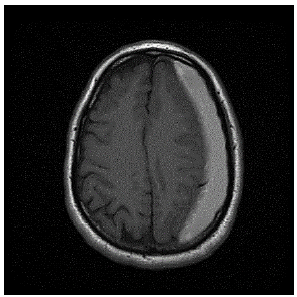

Paciente idoso, de 81 anos, sexo masculino, apresenta queda da própria altura ao se levantar rápido da cama no período noturno para ir ao banheiro, fato que estava acontecendo de forma frequente, pois estava com a diabetes descompensada nos últimos quatro meses. Porém, dessa vez, durante a queda, ele bateu a cabeça na cômoda do quarto, o que preocupou sua filha. Foi levado ao pronto-socorro do hospital mais próximo de sua casa. Além da Diabetes mellitus do tipo 2, o paciente também é hipertenso; ansioso; e, cardiopata, tendo colocado um stent farmacológico em uma de suas coronárias há 7 meses e, por este motivo, fazia uso de AAS e clopidogrel. O paciente realizou a seguinte tomografia computadorizada de crânio:

Qual diagnóstico provável do paciente?